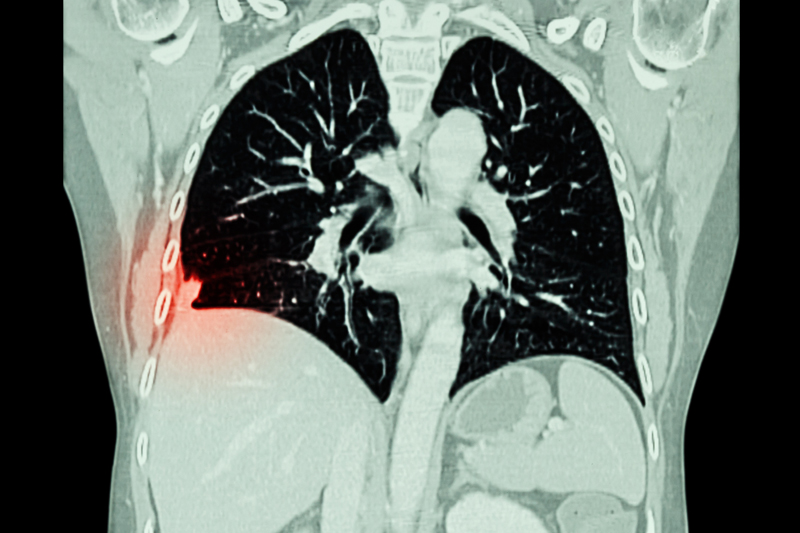

来源:摄图网